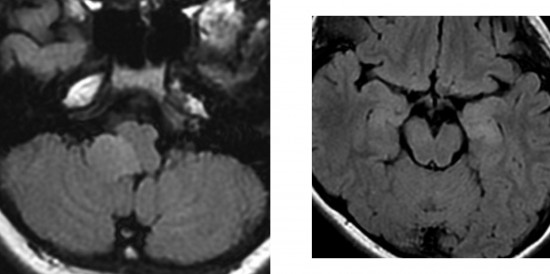

16歳の時のMRI

2年の間に延髄の腫瘍はかなり小さくなりました,これを自然退縮 spontaneous involusion と言います